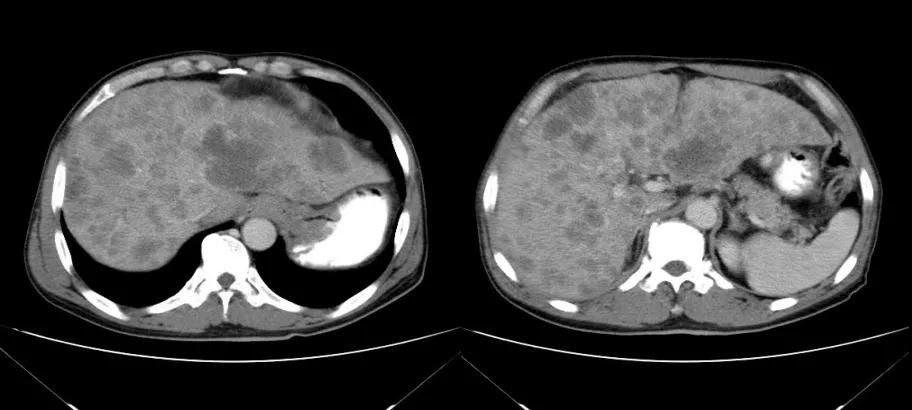

诊治经过:2021年5月16日患者行第三次经皮动脉化疗灌注栓塞术(铂类+氟尿嘧啶)治疗,并继续联合吡咯替尼治疗。结果见图4。

图4

总结:本例患者为胃癌IV期,伴肝转移及淋巴结转移,经介入联合吡咯替尼治疗后,肝转移灶显著缩小。治疗前肿瘤标志为:癌胚抗原3574.3ng/ml、CA12-5 650U/ml、CA19-9 1212U/ml、CA15-3 333U/ml;治疗后肿瘤标志为:癌胚抗原7.6ng/ml、CA12-5 12.8U/ml、CA19-9 17.4U/ml、CA15-3 6.7U/ml。治疗后,肿瘤标志物显著降低,且腹部CT结果显示该患者肝转移病灶较治疗前明显减少。患者目前带瘤总生存达10个月,病情稳定。